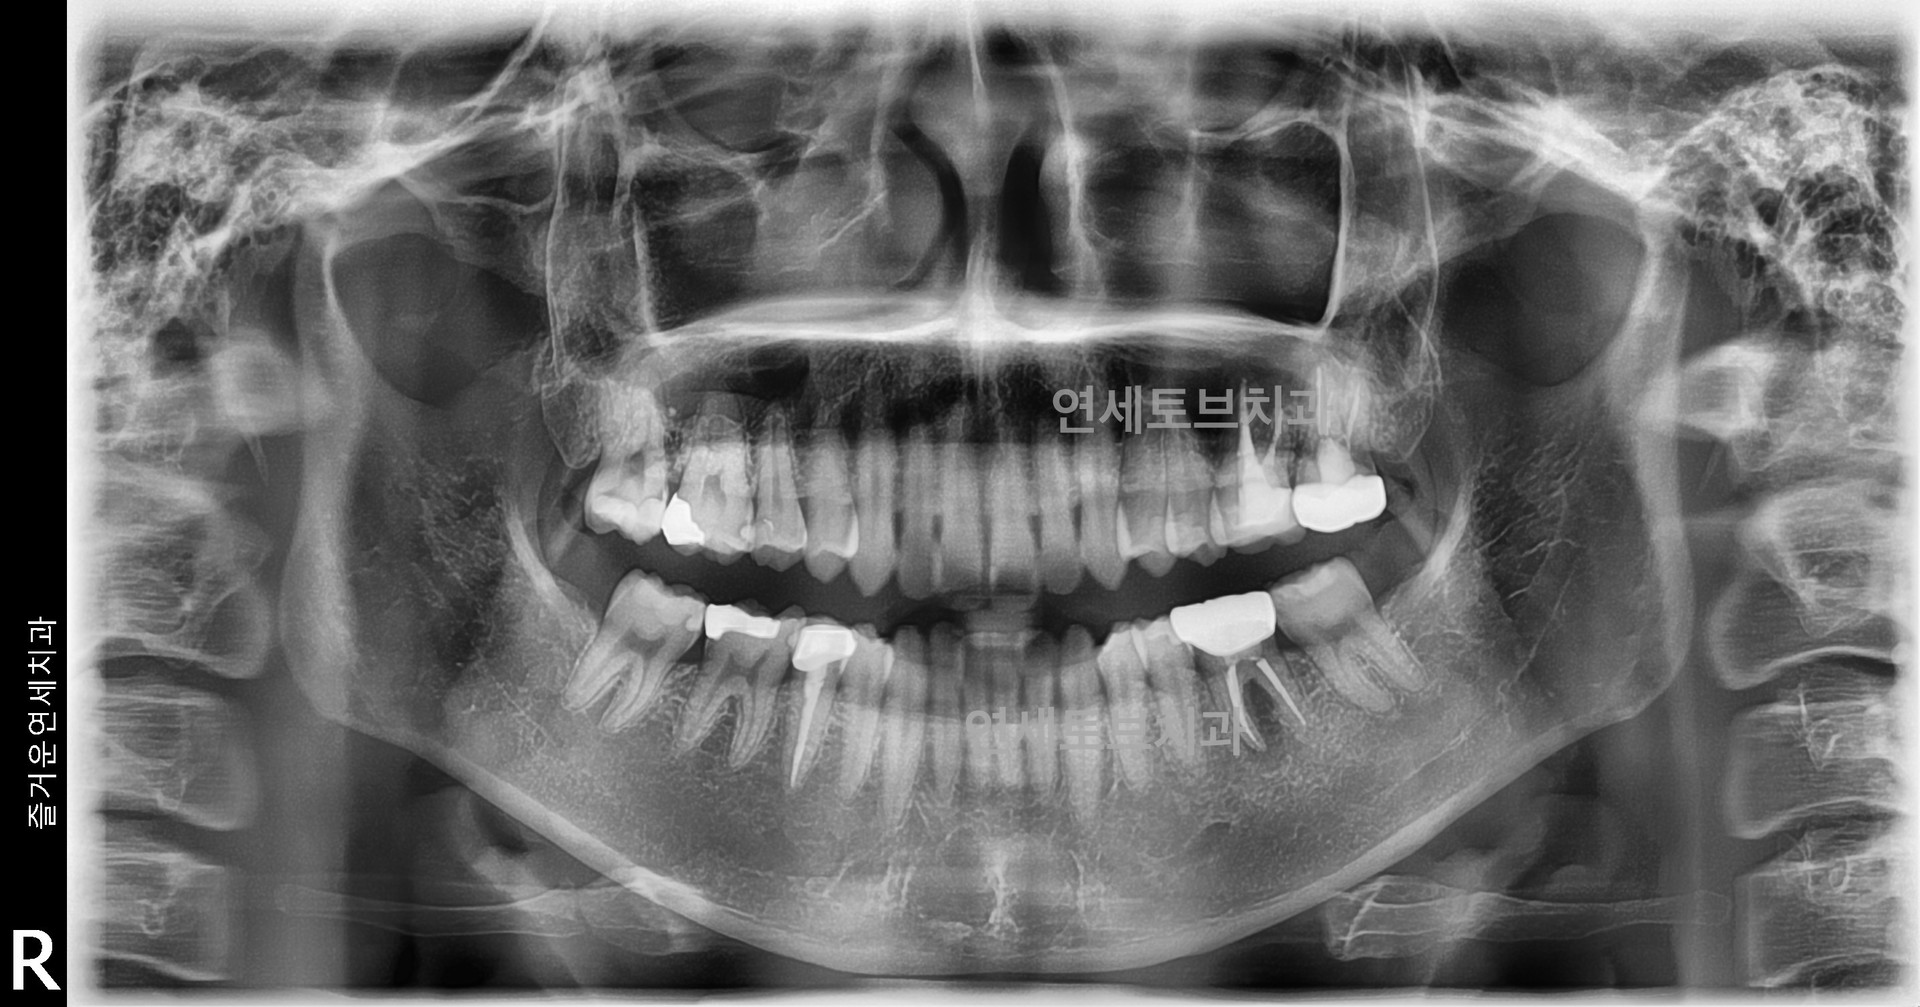

재근관 치료

재근관치료 란?

재근관치료는 기존 신경치료가 실패한 치아를 최대한 보존하는 치료법으로, 치과의사의 숙련도와 치아 상태에 따라 성공률이 달라질 수 있습니다. 치아 보존을 우선한다면 임플란트보다는 재근관치료를 먼저 고려하는 것이 일반적입니다